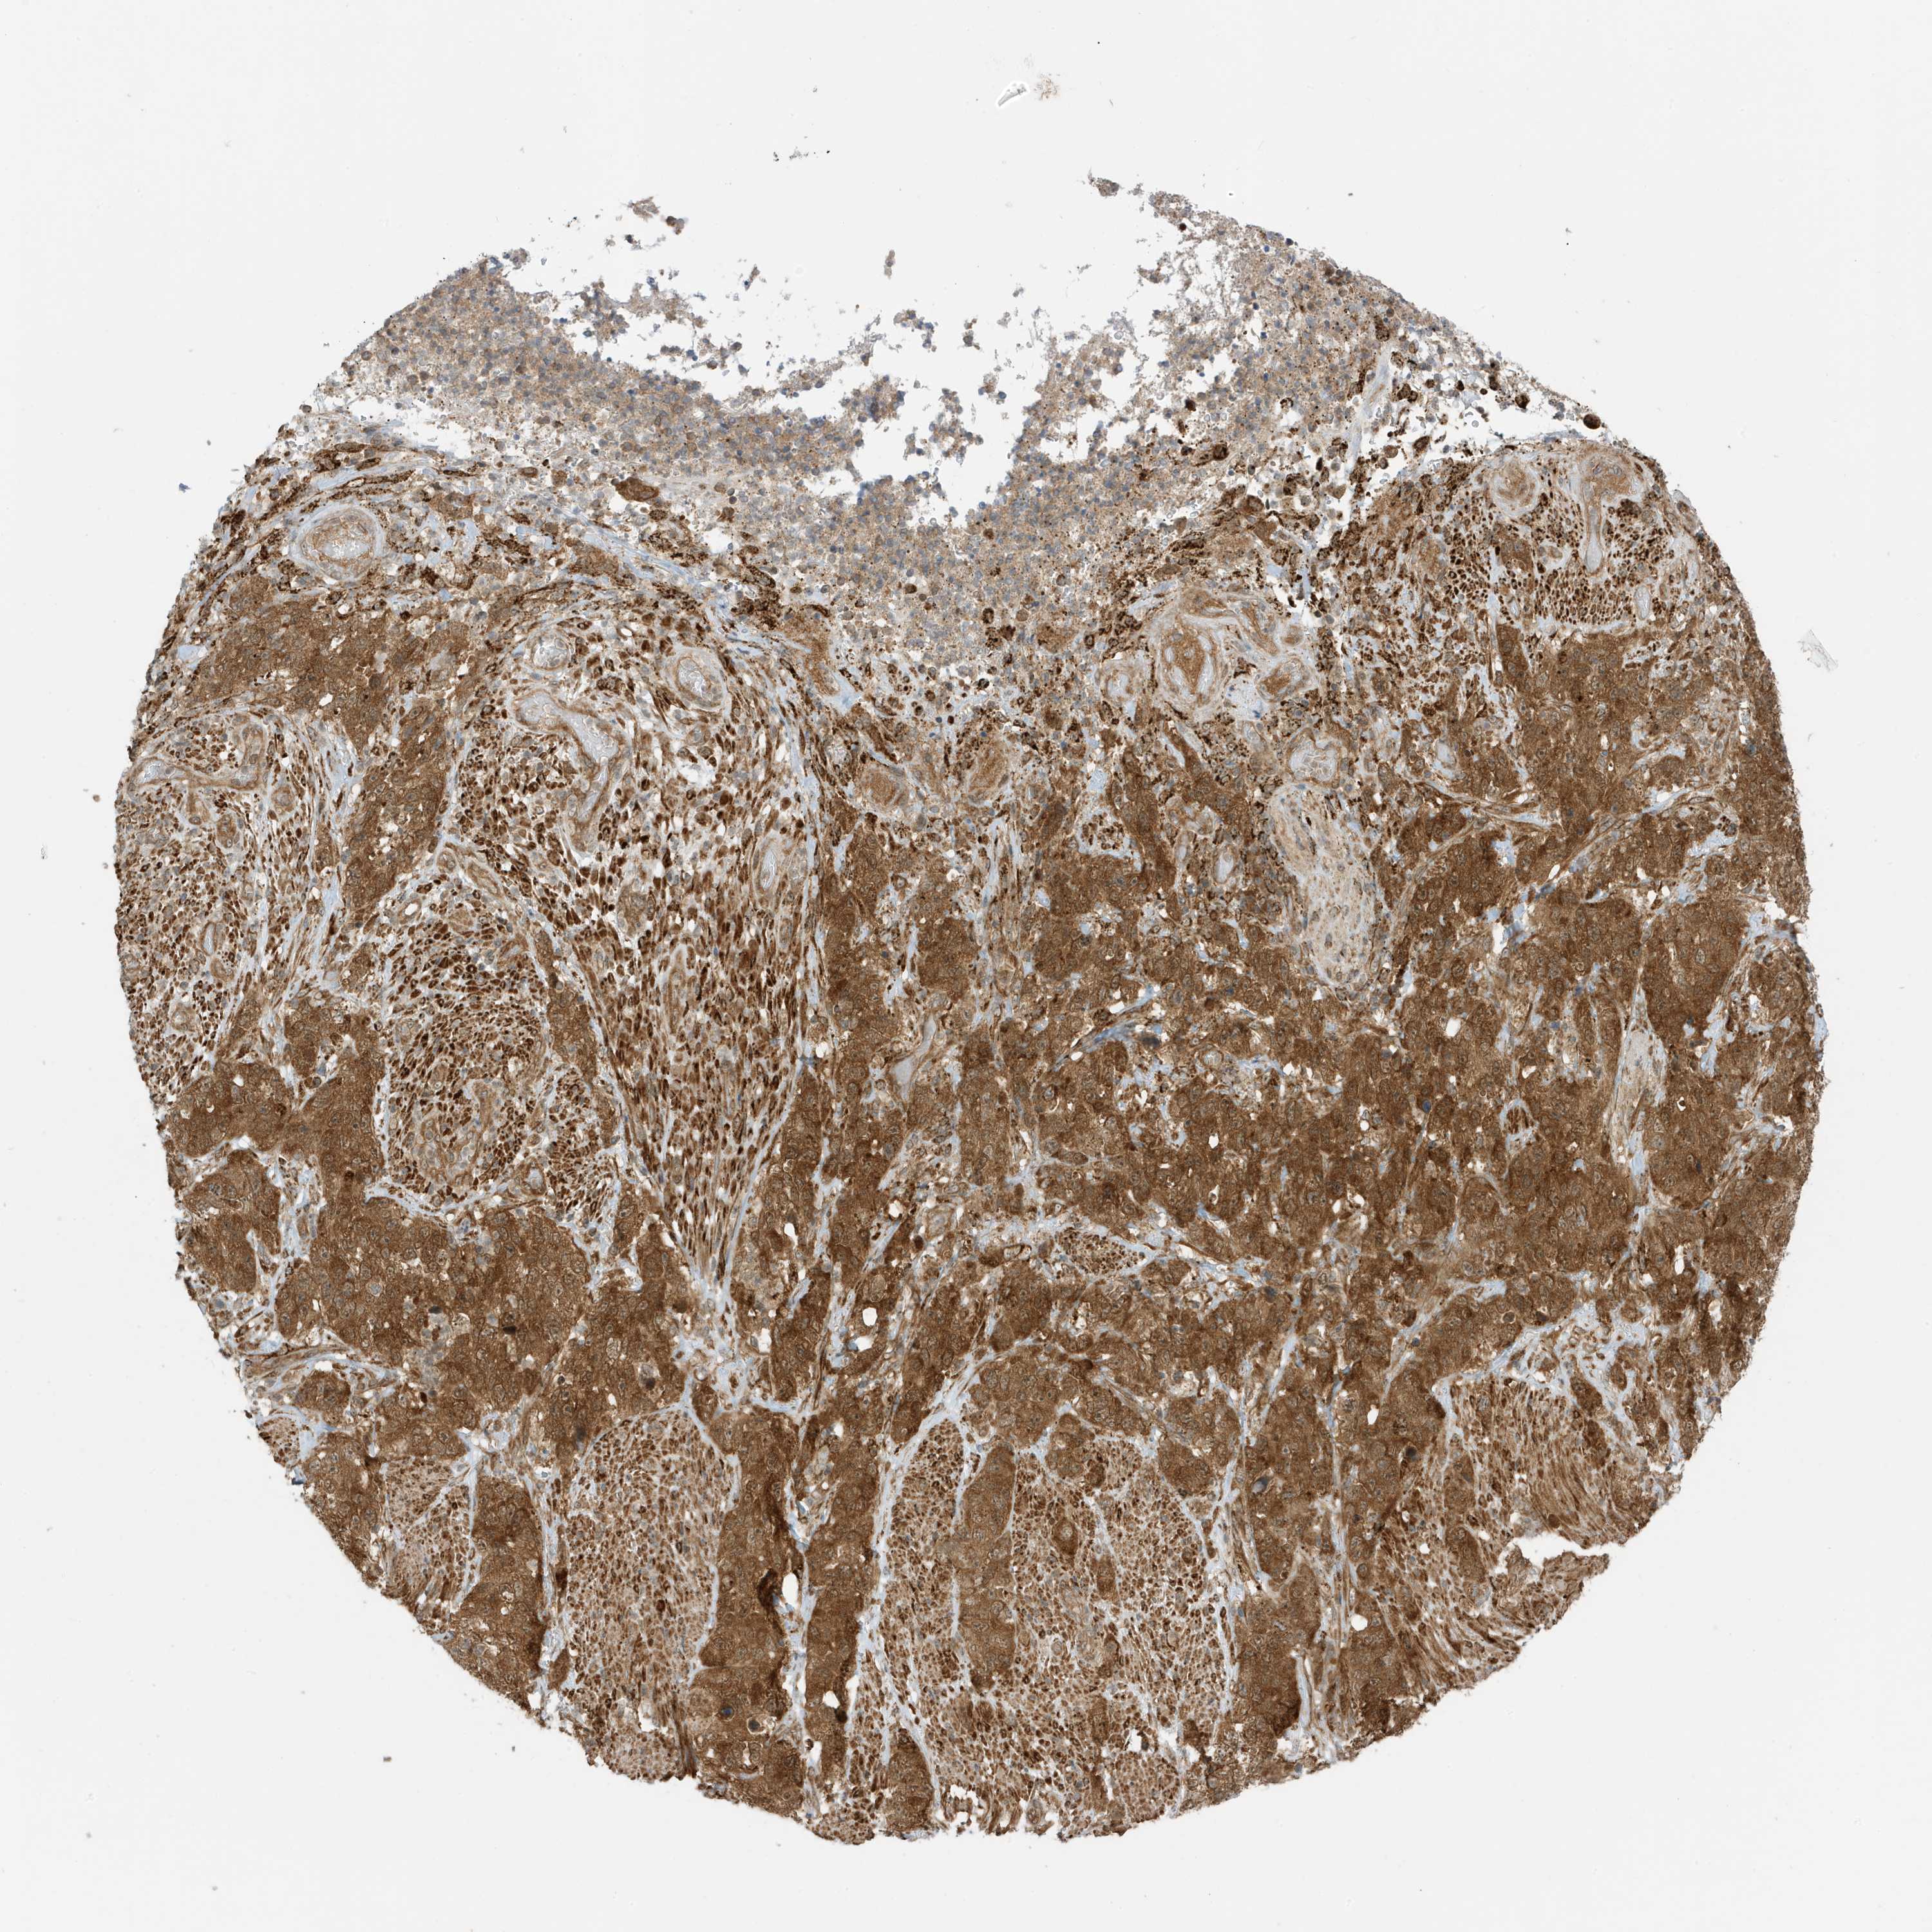

STOMACH CANCER - Protein expressioni

A mouse-over function shows sample information and annotation data. Click on an image to view it in a full screen mode. Samples can be filtered based on level of antibody staining by selecting one or several of the following categories: high, medium, low and not detected. The assay and annotation is described here.

Note that samples used for immunohistochemistry by the Human Protein Atlas do not correspond to samples in the TCGA dataset.

Antibody stainingi

Antibody staining in the annotated cell types in the current human tissue is reported as not detected, low, medium, or high, based on conventional immunohistochemistry profiling in selected tissues. This score is based on the combination of the staining intensity and fraction of stained cells.

Each image is clickable and will lead to virtual microscopy that enables deeper exploration of all samples and also displays staining intensity scores, fraction scores and subcellular localization as well as patient and tissue information for each sample.

Antibody HPA035399

Staining

High

Medium

Low

Not detected

Intensity

Strong

Moderate

Weak

Negative

Quantity

>75%

75%-25%

<25%

None

Location

Nuclear

Cytoplasmic/membranous

Cytoplasmic/membranous,nuclear

Adenocarcinoma, NOS